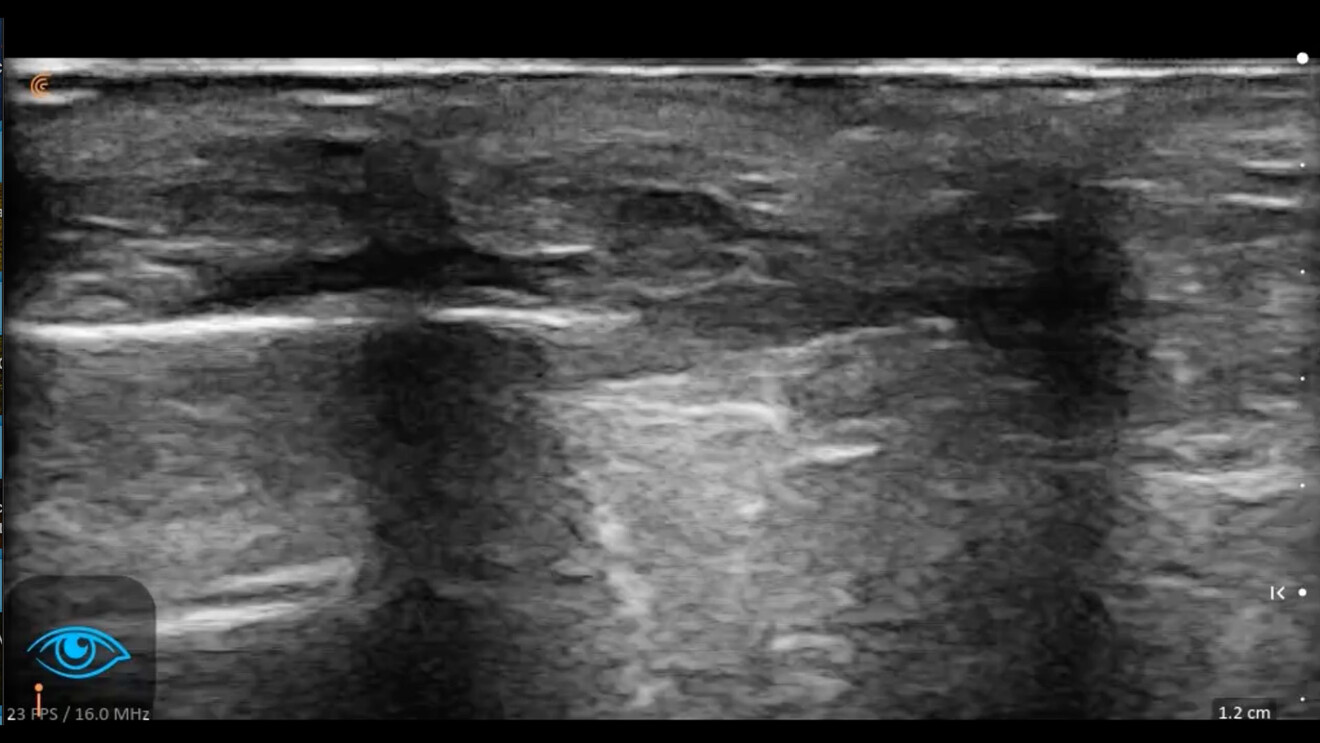

Nel paziente anziano: l’assottigliamento del derma e la progressiva atrofia e il dislocamento dei tessuti adiposi pongono all’operatore la necessità di analisi delle strutture anatomiche del volto strettamente individuali. L’ecografia evita di traumatizzare strutture profonde ormai fragili e permette di identificare con precisione ed evitare di compromettere l’integrità strutturale e la funzione trofica dei vasi arteriosi e venosi.

La mappatura dei vasi del volto e delle strutture anatomiche sensibili consente di seguire percorsi terapeutici più sicuri nelle categorie della medicina estetica in cui l’integrità della barriera cutanea è interrotta inizialmente da un ago e successivamente la prosecuzione del piano terapeutico è affidata ad un ago che inietti tossina botulinica o infiltri filler a base di acido ialuronico di diverse caratteristiche reologiche o a una cannula che produca una subcisione nello strato adiposo superficiale e diffonda acido ialuronico o veicoli fili di biostimolazione o di trazione.

Con l’ausilio e la guida dell’ecografia l’operatore avrà un occhio su tutti gli strati sottocutanei e in particolare concentrerà il suo sguardo e guiderà la propria mano sullo strato che è il suo obiettivo e potrà:

• La sicurezza nelle aree di intervento: la guida ecografica è vitale nelle cosiddette “aree a rischio”. Nel trattamento delle rughe nasali, ad esempio, la consapevolezza dell’anatomia sonografica dell’individuo in tempo reale garantisce che l’iniezione, l’infiltrazione, l’impianto permangano nello strato tissutale previsto. Queste precauzioni evitano che il farmaco non raggiunga o superi il target muscolare previsto o il dispositivo medico coinvolga accidentalmente i vasi di calibro tale da determinare complicanze di natura ischemica o l’impianto del filo sia troppo superficiale o troppo profondo rispetto al piano ottimale.